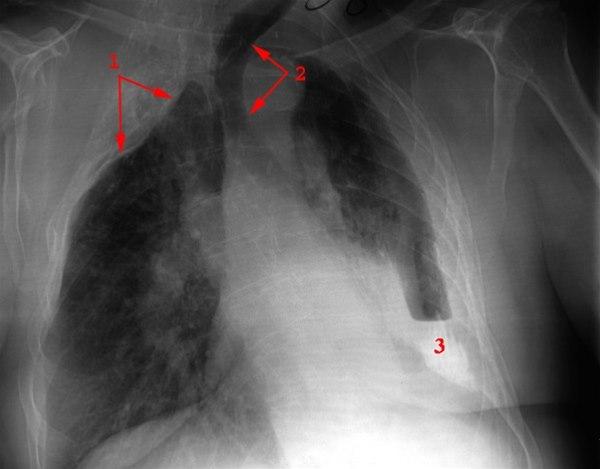

Tbc behandlet med torakoplastikk høyre side (1)

Utbredte parenkymforandringer

- Torakoplastikk høyre side

- Larynx trukket over mot sammenfalt lungeavsnitt

- Svær forkalkning basalt venstre side